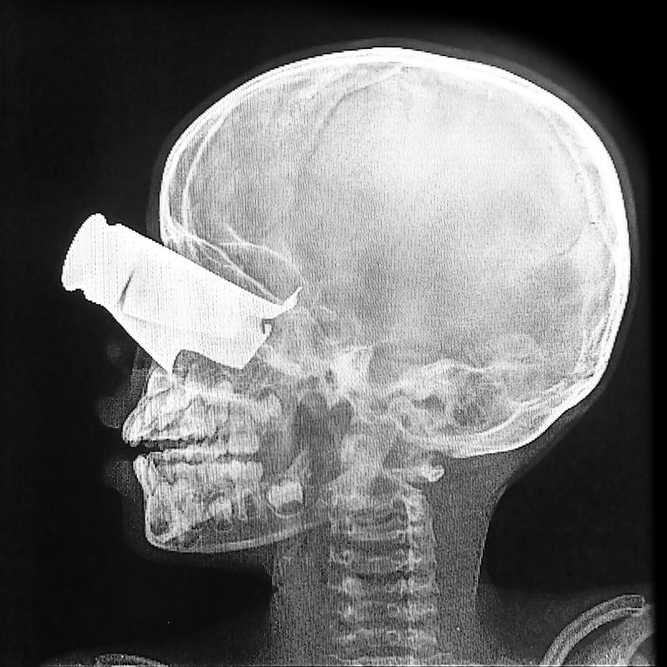

국경없는의사회는 이달 첫 2주 동안 수단 민간 지역에서 흉부 및 복부 관통상, 사지 다발성 골절, 두부 외상, 드론 파편상 등을 입은 환자 167명을 치료했다고 밝혔다. 이는 수단군(SAF)과 신속지원군(RSF)이 수단 전역에서 드론 공격을 이어가면서 발생한 피해에 따른 것이다.

버지니아 모네티 국경없는의사회 티네 프로젝트 의료 코디네이터는 “치료한 환자들 가운데 9세 남아는 눈에 커다란 파편상과 안면부에 광범위한 골절을 입었으며 손가락 두 개가 절단된 상태로 도착했다”며 “아이는 장시간 이동 과정에서 먼지에 노출됐고 극심한 통증을 호소했다. 최선의 치료를 받아도 장기적인 장애가 남을 가능성이 크다”고 덧붙였다.